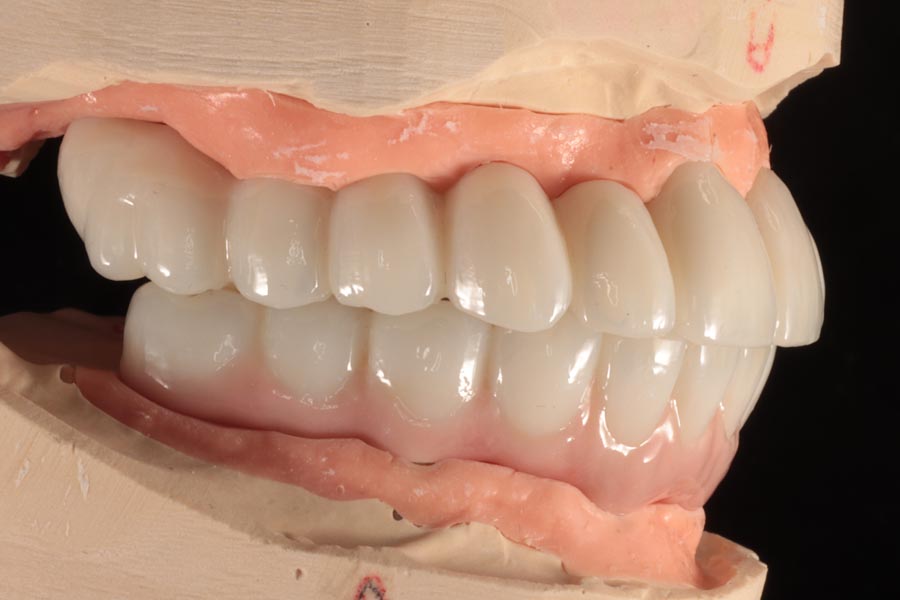

The definitive bridges are delivered, the bite is verified, and the screws are torqued down firmly. The final result is strong, functional, and esthetic restorations that will serve the patient well for years to come.